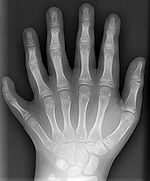

Some mutations occur in so-called regulatory genes. Changes in these can have large effects on the phenotype of the individual because they regulate the function of many other genes. Most, but not all, mutations in regulatory genes result in non-viable zygotes. Examples of nonlethal regulatory mutations occur in HOX genes in humans, which can result in a cervical rib or polydactyly, an increase in the number of fingers or toes. When such mutations result in a higher fitness, natural selection will favour these phenotypes and the novel trait will spread in the population.